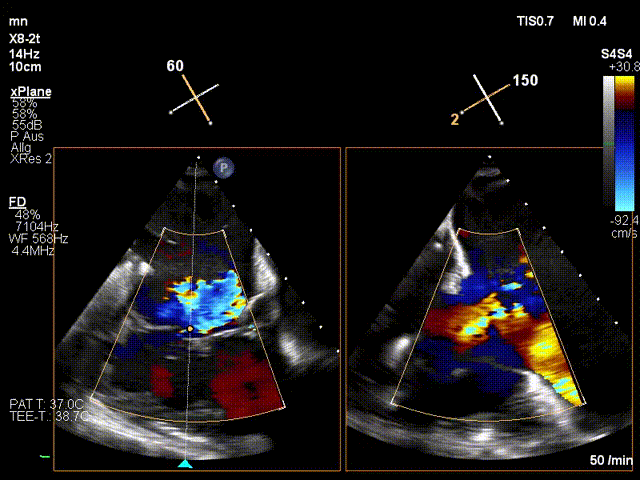

手術(shù)在全麻狀態(tài)下進(jìn)行。在加拿大圣保羅醫(yī)院的Anson Cheung教授的指導(dǎo)參與下,術(shù)者采用經(jīng)右側(cè)頸靜脈入路的方式將輸送器送入患者心臟內(nèi),在TEE及DSA引導(dǎo)下調(diào)整輸送器頭端角度,使得輸送器與三尖瓣瓣環(huán)平面垂直。在輸送器進(jìn)入右心室后釋放室間隔錨定裝置,而后釋放瓣葉夾持件(2個(gè)耳片結(jié)構(gòu))成垂直狀態(tài)。在TEE及DSA確定夾持件固定至三尖瓣葉根部且位于右室側(cè)后釋放人工瓣心房側(cè)盤片。隨后調(diào)整瓣膜同軸性以及室間隔錨定件位置(貼合室間隔),前推藏針管并固定,進(jìn)而釋放室間隔錨定裝置,并再次確認(rèn)瓣膜位置、穩(wěn)定性及同軸性,合攏輸送鞘后撤出輸送器,完成LuX-Valve Plus人工三尖瓣瓣膜的植入。

LuX-Valve Plus經(jīng)血管三尖瓣置換系統(tǒng)本次“出海”圓滿完成,術(shù)后Jörg Hausleiter教授對(duì)LuX-Valve Plus經(jīng)血管三尖瓣置換系統(tǒng)的器械性能和治療效果大為稱贊,認(rèn)為LuX-Valve Plus的手術(shù)體驗(yàn)非常好。術(shù)后即刻超聲顯示三尖瓣反流消失,血流動(dòng)力學(xué)改善顯著,患者恢復(fù)快。Anson Cheung教授也肯定了LuX-Valve Plus術(shù)中操作的便捷性,認(rèn)為LuX-Valve Plus容錯(cuò)率高,對(duì)術(shù)中影像的依賴較小,后期希望可以更多的應(yīng)用LuX-Valve Plus三尖瓣置換系統(tǒng)于臨床實(shí)踐,讓更多的三尖瓣重度反流患者盡早獲益,改善預(yù)后。